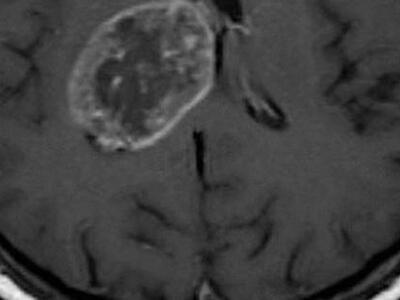

WELL BEING / 21/03/2014, 21:45 Νέα τεχνική καταπολέμησης του καρκίνου με «ανατίναξη» καρκινικών κυττάρων